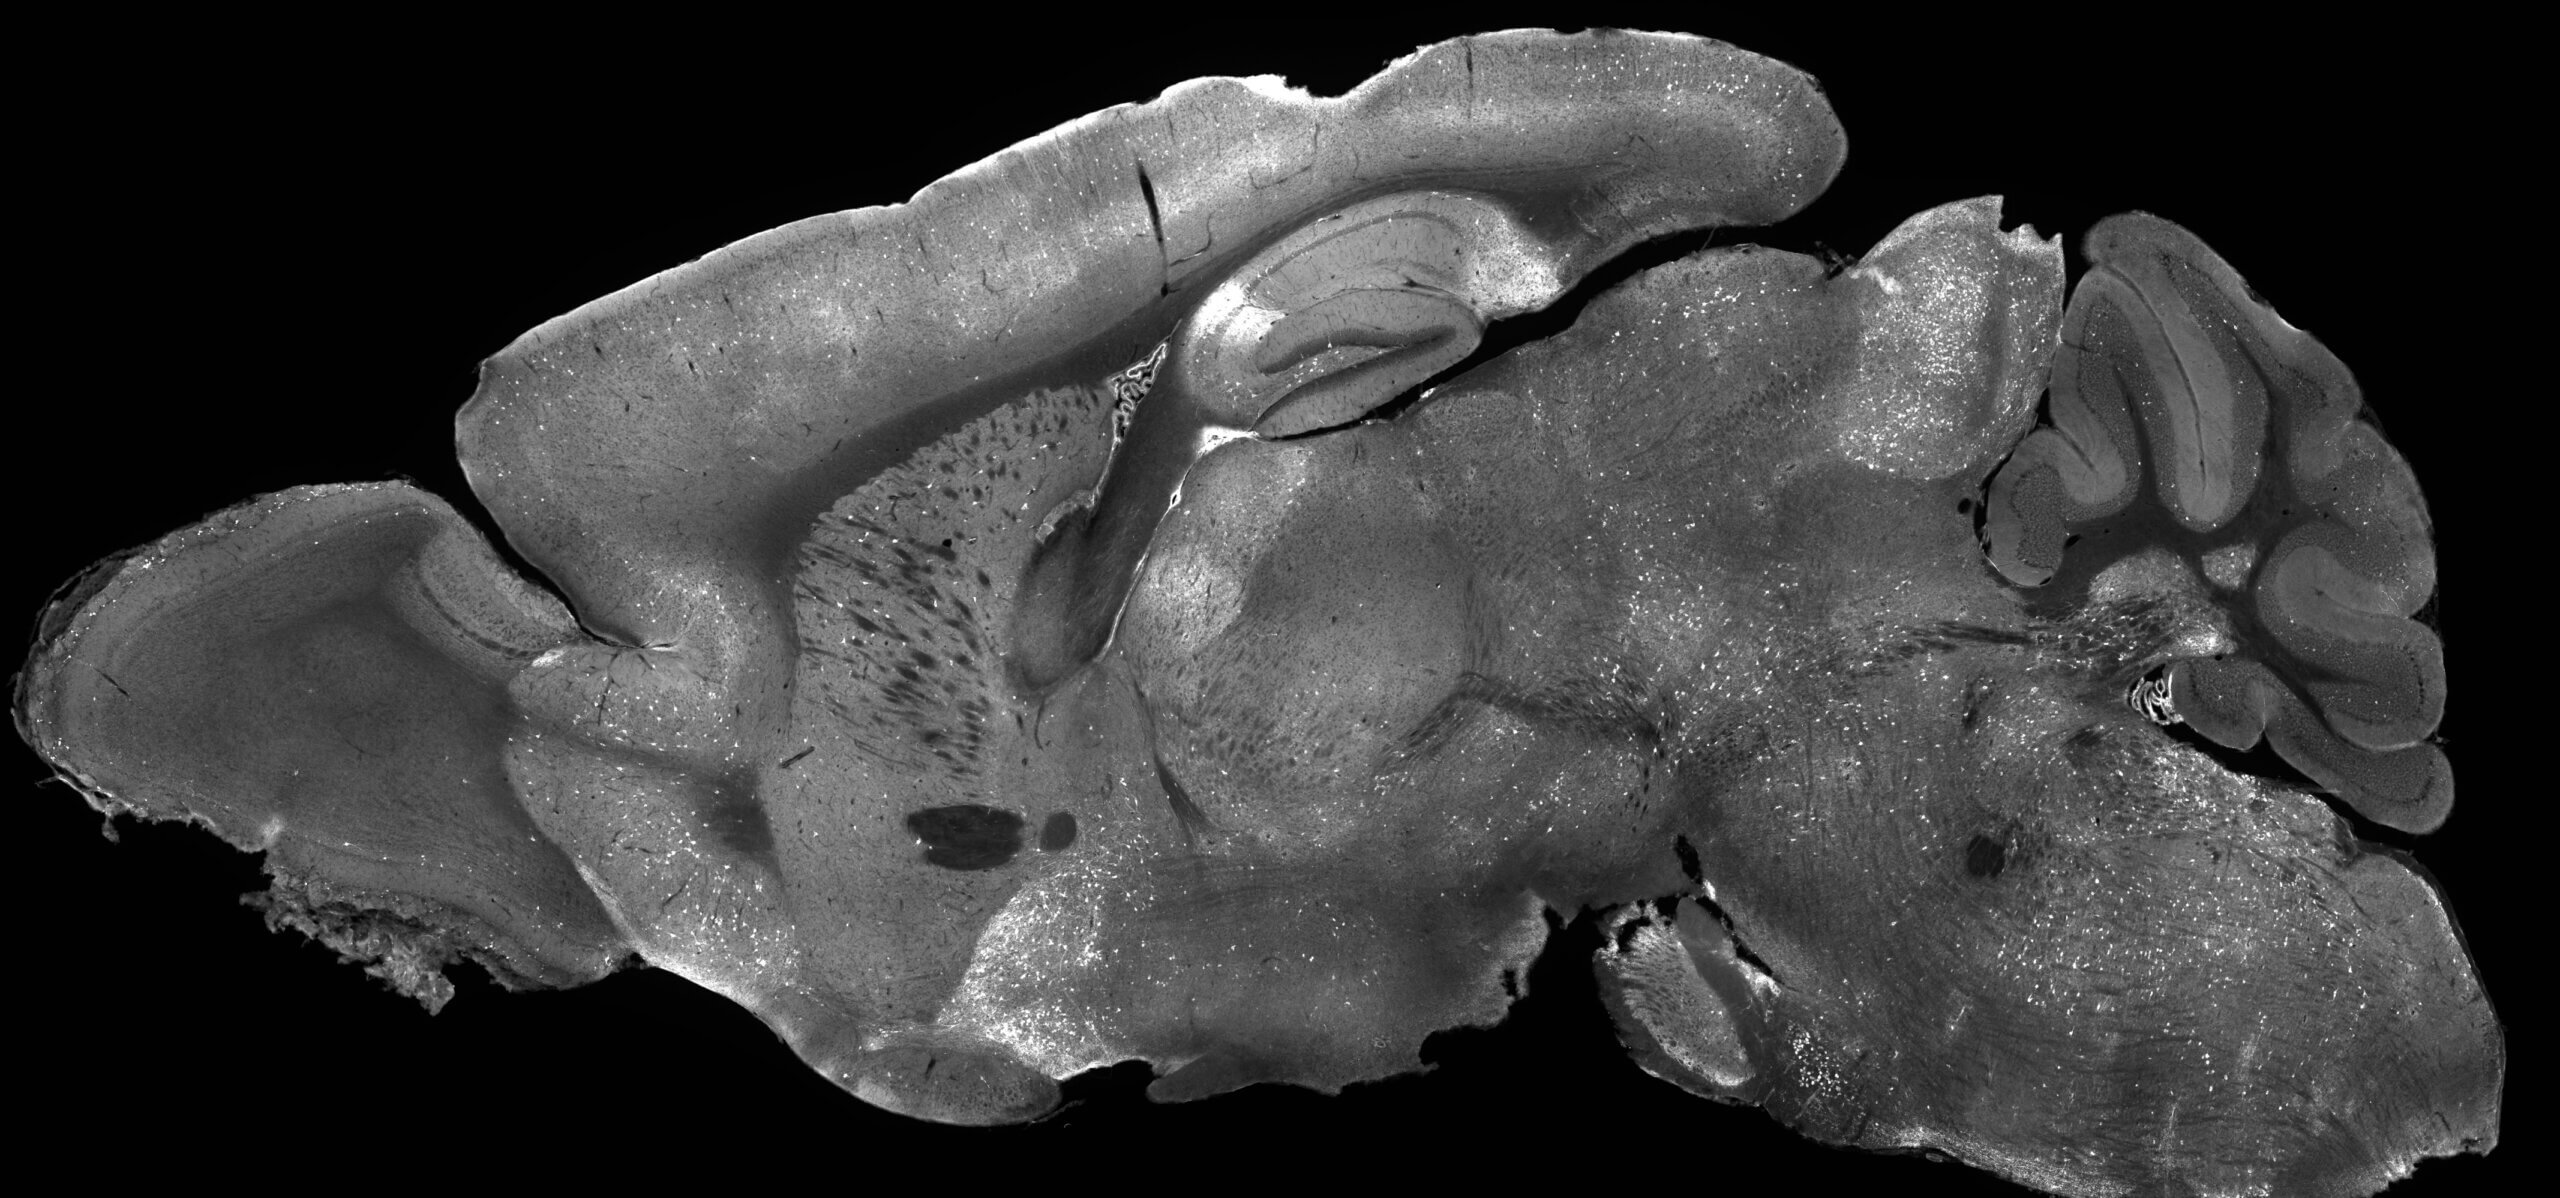

Black and white image of brain slice from a mouse brain

Mouse brain image glowing with experimental gene supplementation therapy highlighting how AAV delivers treatment across the entire brain (Photo credit: Allen Institute/Andrew Clark)